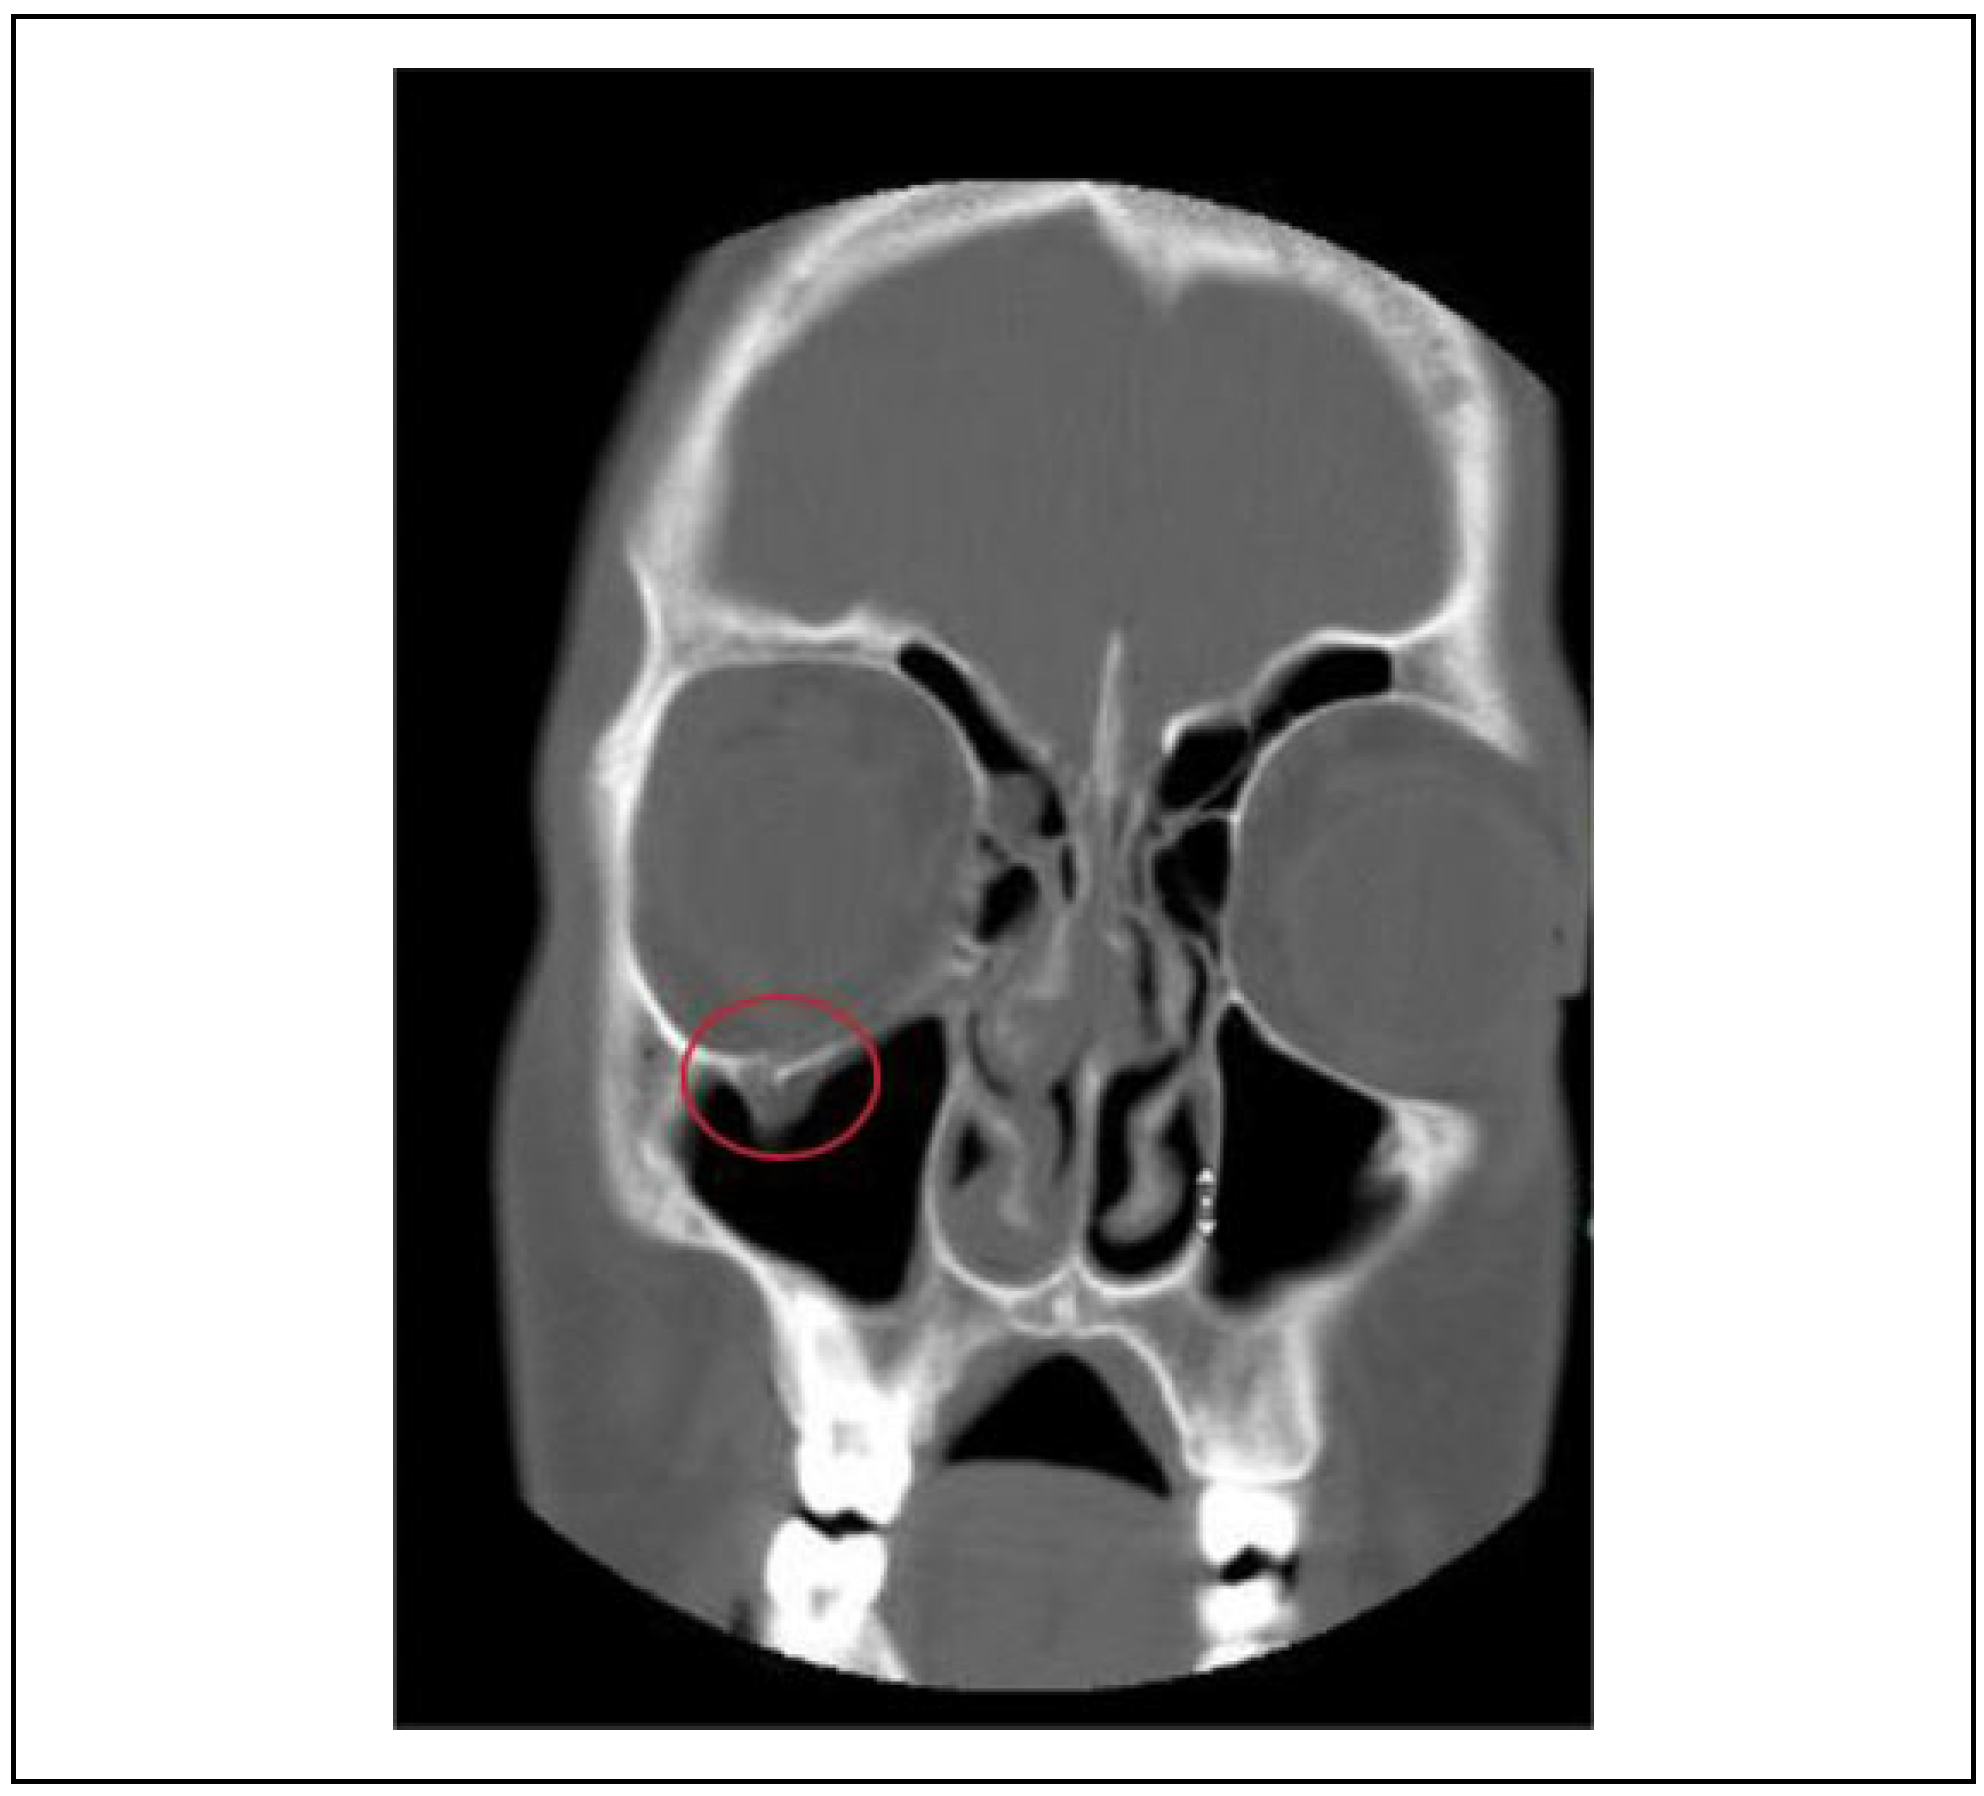

Abbreviations: GSW, gunshot wound; Inj, injury; MVC: motor vehicle collision.We also analyzed the timing of surgery for each type of periorbital injury suffered. Most interventions were performed in an elective setting, although in 22% cases, surgical intervention was performed in an emergent fashion. The most common periorbital injury that required emergent surgical management was muscle entrapment secondary to orbital fractures (Figure 2). Eighty-seven percent of the pediatric patients who developed muscle entrapment had an associated orbital floor fracture; one patient had muscle entrapment caused by a medial orbital wall defect.

Figure 2.

Pediatric patient with right-sided orbital floor fracture with muscle entrapment.